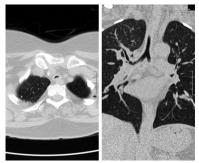

A 50-year-old female patient was evaluated at our center in February 2016 with history of hearing loss, inflammatory arthritis, and saddle nose for four years and new-onset worsening of hoarseness of voice, cough and breathlessness for three months. She was being treated as GPA based on clinical features and anti-myeloperoxidase (MPO) positivity with oral steroids and weekly methotrexate of 22.5 mg. Further evaluation showed normal complete blood count but raised erythrocyte sedimentation rate with normal urine examination, renal functions and liver functions. Chest X-ray did not show any infiltrates. Cardiac evaluation was normal. High-resolution computed tomography (HRCT) of the chest with neck cuts showed circumferential thickening of trachea (Figure 1).